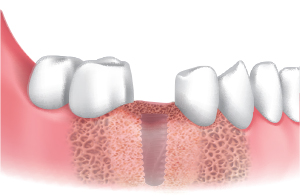

A Clinical Case using Ø3.5/4.0 Harvesting Drill

by Dr. Soohong Kim, DDS, Ph.D

-

Drilling at 300 rpm with irrigation was carried out after marking implant and harvesting position.

The Silicone Shield was brought into close contact with various types of bone level and prevented bone chip loss.

The amount of bone taken was easily ascertained, through the transparent Silicone Shield.

The bone was transferred to bone dish after disassembling the Silicone Shield and Stopper.

The amount of the bone was much more than expected.

After the implant placement, healing abutments were connected and carried out GBR in the defected area.

* 2 Step Harvesting : Drilling to 7mm is recommended after transferring bone chips to bowl since the Stopper & Silicone Shield are fully filled with bone chips while 4mm drilling.